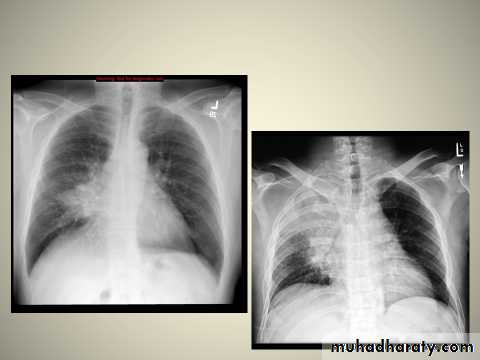

Right middle lobe collapse has distinctive features, and is usually relatively easily identified.

Radiographic features

Chest radiograph

Frontal chest XR showing opasity cause obscuration of the RT cardiac border

Lateral chest XR film the opacity is tongue like shape

versus (triangular in shape) in RT middle lobe consolidation seen in lateral chest XR film

Non-specific signs indicating right sided atelectasis may also be present (although due to the small size of the right middle lobe they may well be subtle). They include:

elevation of the hemidiaphragm

crowding of the right sided ribs

shift of the mediastinum to the right